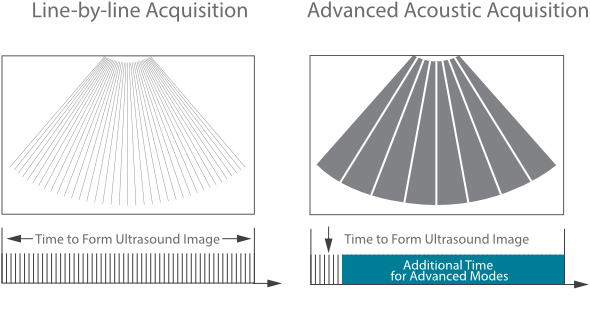

Mindray? ??? ??? ?? ??? ???? ??? ?? ??? ??? ????? ??? ????. ?? ???? ZONE Sonography? ??? ???? ?? Resona 7? ??? ZST+ ???? ?? ?? ? ?? ??? ????? ?? ??? ??? ??? ? ?? ????.